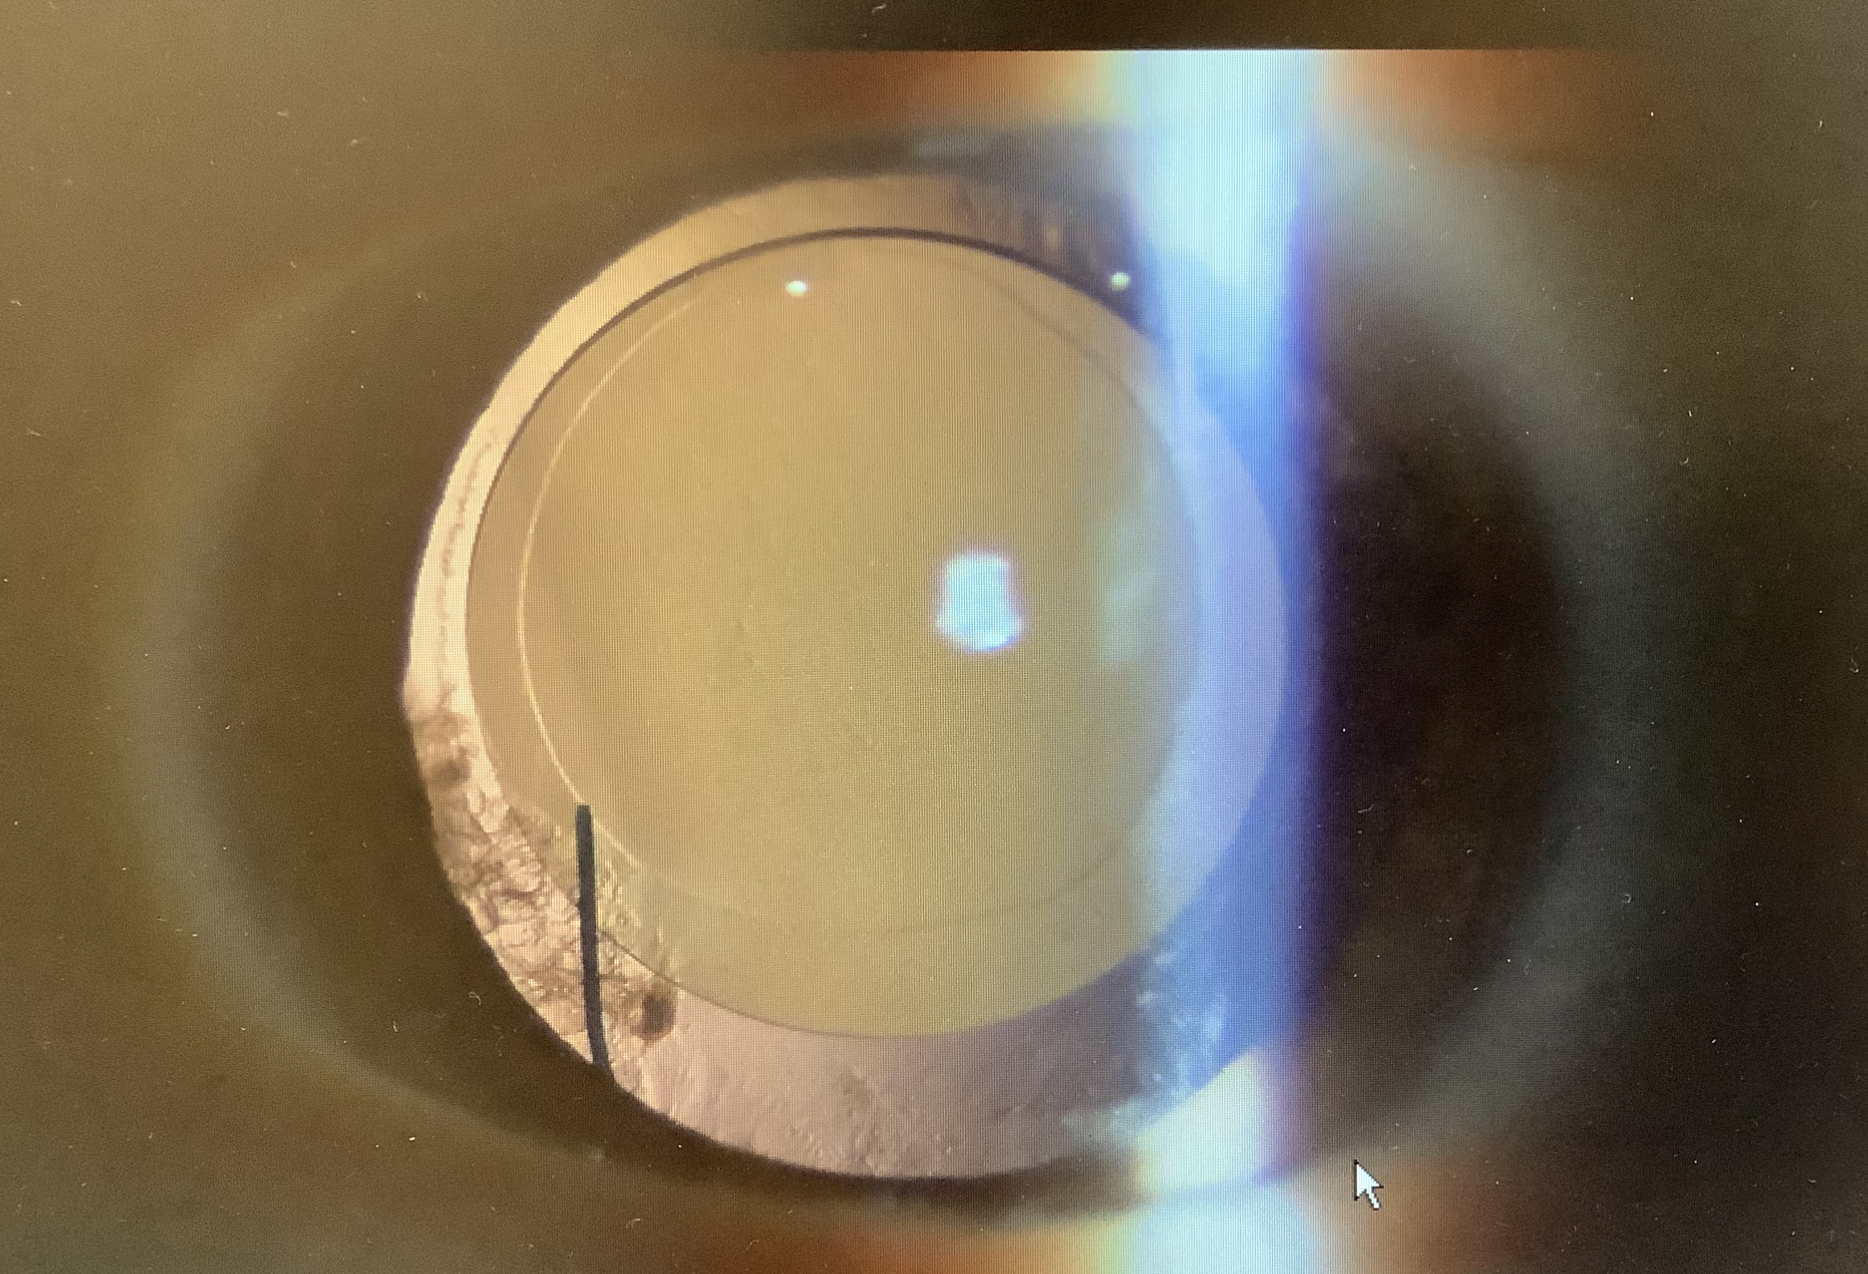

もう一人も50代の女性で、11月に多焦点レンズ(Synergy)での白内障手術を受け、視力自体は良好なものの、夜間のハロー・グレアが辛く車の運転が厳しく困っているとのことでのご来院でした。

最初の方は、単焦点で3ピースタイプのレンズが使われており、癒着も少ないですし、時間が経ってもある程度安全にレンズ交換ができそうでしたが、もう一人の方は前嚢切開も小さめで、前嚢の裏側の混濁も目立ち、癒着が若干強そうな印象があり、あまり先にしない方が入れ換えの手術はしやすそうな所見でした。ハローグレアは慣れてくることもあるので、少し様子を見たいところではありますが、感じやすい方にはかなり辛い見え方になってしまうため、長くとも3か月程度で入れ換えをする方が多いかと思います。この患者さまも早めに換えて欲しいとご希望もあり、また、眼の所見上も早めが望ましかったので、2月の初めに手術を予定させていただきました。